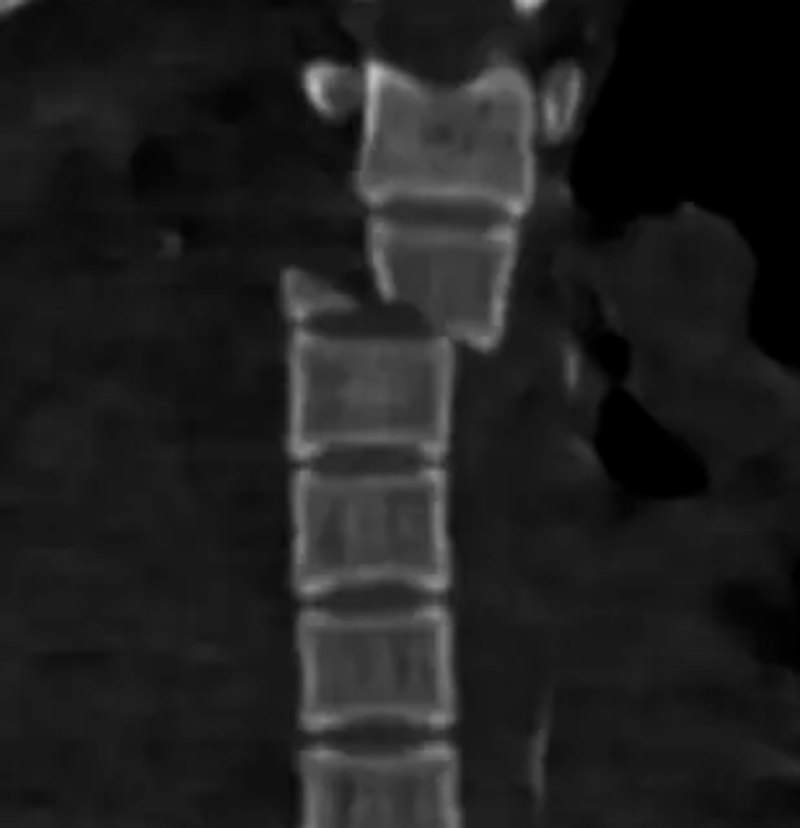

文章配圖

△胸4椎體爆裂性骨折伴脫位。

胸12椎體爆裂性骨折,骨折碎塊壓迫椎管。